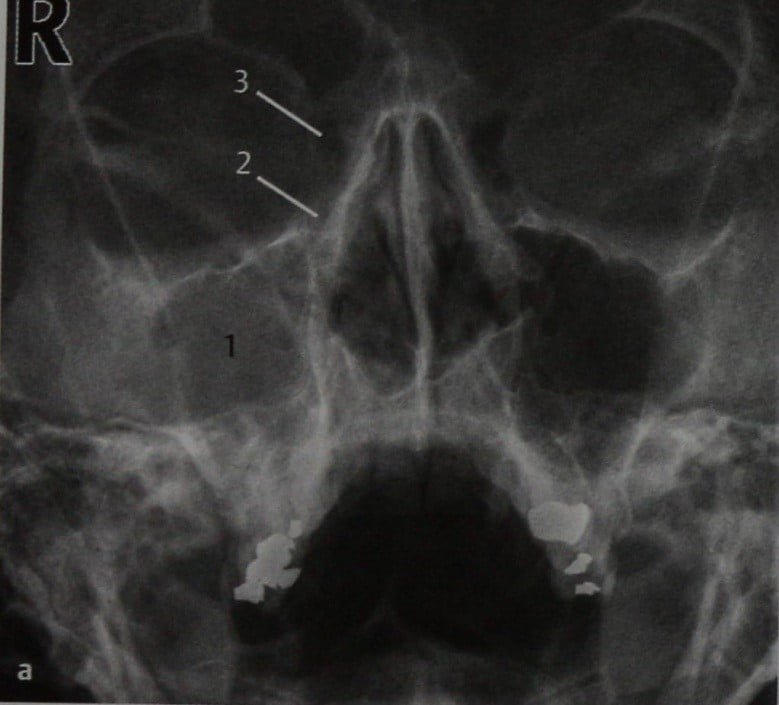

КТ-снимки хронического этмоидита: подробная визуализация

Раздел: Фотодневник открытий